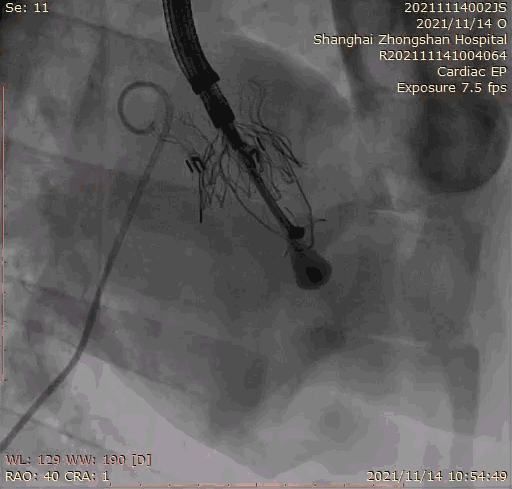

2021年11月14日星期日,復旦大學附屬中山醫院(以下簡稱中山醫院)葛均波院士團隊成功應用經血管介入三尖瓣置換產品Lux-Valve Plus完成臨床前研究,并獲得圓滿成功!此次研究的成功預示經血管三尖瓣產品Lux-Valve Plus已完成臨床前準備,即將開啟后期的正式臨床研究!

上海中山醫院葛均波院士、錢菊英院長、周達新教授、潘文志教授、潘翠珍教授、李偉教授共同完成此次臨床前研究。術后葛均波院士對Lux-Valve Plus的器械操作性能給予了高度評價,DSA和超聲影像也顯示出在本次研究中Lux-Valve Plus的安全性和有效性俱佳。

本次臨床前研究經右側頸靜脈置入LuX-Valve Plus輸送系統可調彎鞘管,在DSA及超聲引導下將人工三尖瓣瓣膜植入到原有三尖瓣位置,利用獨特的錨定技術將人工瓣膜支架可靠固定在預定的位置。